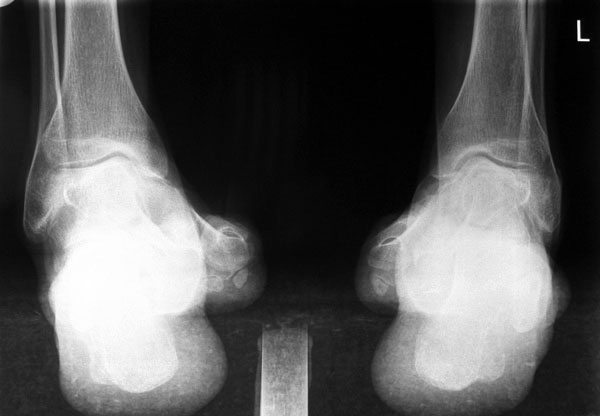

• Fuß belastet dp und seitlich (Abb. 14 und 15)

• Saltzman view (Abb. 16)

Typische Merkmale der Standard-dp-Röntgenaufnahme des Fußes im Stand

• Talus und Calcaneus verlaufen fast parallel

• Os naviculare ist gegenüber dem Talus nach medial gedrängt

• Metatarsalia überlappen sich basisnah

• Metatarsale I erscheint verkürzt

• Metatarsus adductus

Typische Merkmale des Saltzman View

• Calcaneus steht varisch zur Tibialängsachse

• Der erste Zehenstrahl ist medial erkennbar

• Konsekutive varische Gelenklinie des oberen Sprunggelenkes